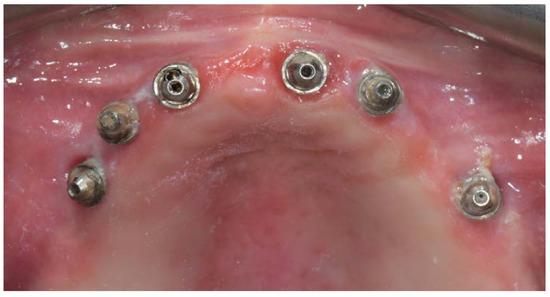

Before definitive impression, multi-unit abutments were unscrewed, the implant connections were cleaned, and six OT Equator Titanium Abutments (Rhein’83, Bologna, Italy) with TiN coating were screwed (Figure 6), according to the manufacturer. Immediately after, the patient received a digital impression (CS 3600 intraoral scanner, Carestream Dental, Milan, Italy), taken at abutment level (Figure 7), using dedicated scan abutments (OT Equator Titanium Scan Abutment, Rhein’83). However, overlapping of the captured images failed to produce an accurate impression, maybe due to the disparallelism of the implant ranging from 65° to 86°. Hence, a prototype model was created and a convention gypsum impression [16] with a customized impression tray was taken at abutment level using conventional impression coping (Titanium Impression Coping, Rhein’83; Figure 8 and Figure 9). Esthetics, phonetics, the occlusal vertical dimension, and the centric relation were verified and approved by both the clinician and the patient (Figure 10 and Figure 11). Only after that, a definitive cast, implant position, and esthetic try-in were digitalized and a CAD/CAM titanium bar (NewAncorvis, Bologna, Italy) was anatomically designed with a dedicated software (Exocad DentalCAD, Exocad, Darmstadt, Germany) by a certified dental technician (MA), according to the prosthetic contours and the implant position. Three projects were created with a three-, two-, or one-piece CAD/CAM titanium bar, respectively (Figure 11b). Each of these projects failed to create an accurate titanium bar able to respect the minimum restorative space required by the prosthetic volume of the tried prosthesis, due to the multiple components involved (attachment system, prosthetic framework, artificial acrylic composite teeth, and pink acrylic base). Hence, a fourth project was created with a CAD/CAM titanium bar designed for a fixed screw-retained restoration, initially excluded due to the implant disparallelism. In order to overcome the undercuts created by the tilted implants, and to produce a passive-fit CAD/CAM titanium bar, abutments with an extragrade system were applied (Figure 11c). Extragrade is a special titanium abutment which has the possibility of entering, even in cases of strong disparallelisms, thanks to its internal design. On a large number of implants (those positioned worse from the point of view of the emergence profile), we cannot put the through screw. In this case, the abutment will be retained by the white Seeger only. The number of abutments without screws was limited to two, according to the manufacturer and considering the overall number of placed implants. Moreover, an angulated screw channel concept was applied to avoid the access hole in the vestibular area of the anterior teeth, moving the access holes in the pink area of the hybrid prosthesis. The fit of the implant bar was clinically and radiographically tested in the patient’s mouth, according to established criteria ([17,18,19]; Figure 12). It was important to position the flat surfaces of the abutment-bar connections in correspondence with the undercut created by the inclination of the implant; the flat surface indicates the location of the extragrade bevel, which allows the framework to overcome the undercuts created by the tilted implants. After that, an interocclusal record was taken in centric relation, and the prosthesis was delivered. The screw-retained fixed complete implant-supported prosthesis was seated in the patient’s mouth using the snap-on function offered served by the Seeger System (Figure 13). Four out of six screws were tightened according to the manufacturer, and the screw-holes were closed using composite pink materials. Finally, the occlusion was adjusted and radiographs were taken. The patient was scheduled for hygiene maintenance and control every 4 months (Figure 14, Figure 15 and Figure 16).

Figure 6.

OT Equator used as abutment for the fixed prosthesis according to the OT Bridge system.